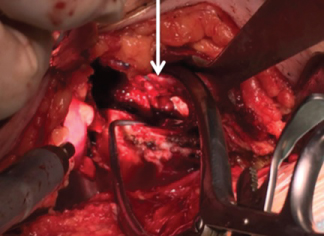

With the hip in 30-45° of flexion and the surgeon sitting on the contralateral side of the lesion, an 8-10-centimeter-long horizontal incision is made two centimeters above the pubic symphysis. The linea alba is opened in a craniocaudal direction and the rectus femoris on the same side of the fracture is subperiosteally detached, exposing the pubic symphysis and the superior pubic ramus. Subsequently, the Retzius space can be accessed after reflecting the bladder to protect it from injury. From 4 to 9 cm lateral to the pubic symphysis, 50-84% of patients present with a so-called corona mortis [13-15], a vascular anastomosis between the obturator and the external iliac artery (Figure 1). This structure must be either ligated or electrocoagulated as it is a potentially dangerous source of bleeding.

Figure 1: Cadaveric image: Corona Mortis (arrow). View Figure 1